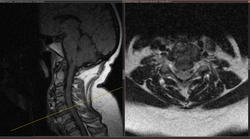

Добавлены данные МРТ:

Приложения:

t1t2.jpgt2t1.jpgt2t2.jpg